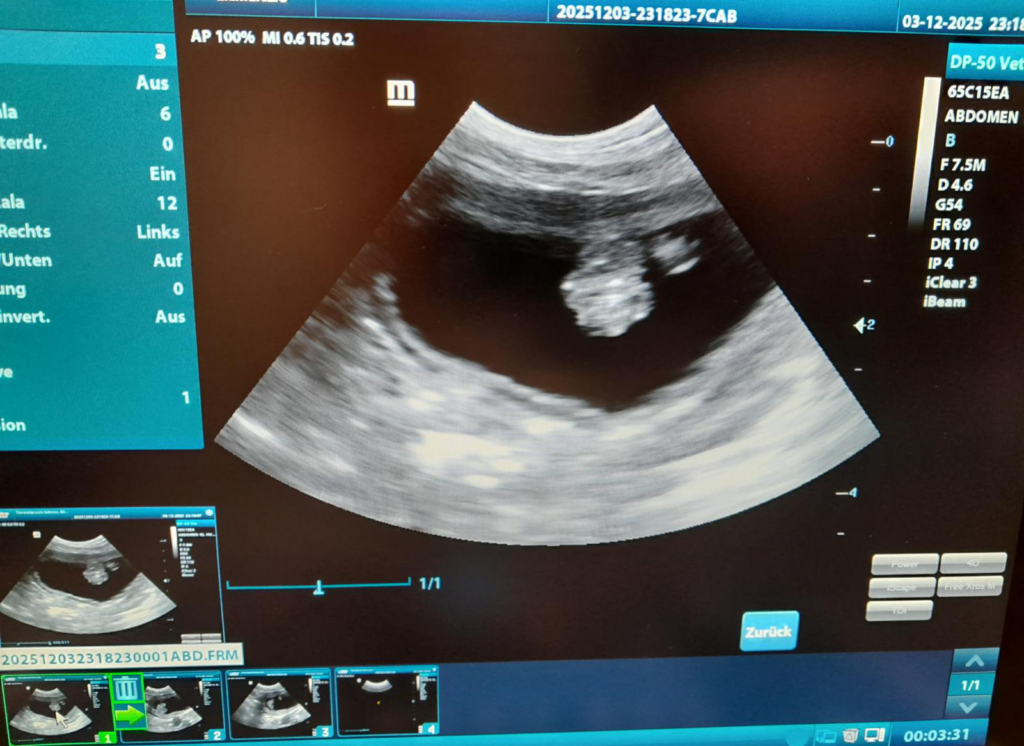

Ultraschall-Untersuchung

Vor allem zur detaillierten Beurteilung der inneren Organe ist eine Ultraschall-Untersuchung der Bauchhöhle sinnvoll. Ergänzend zur Blutuntersuchung liefern die Ultraschall-Befunde häufig wertvolle Hinweise zur richtigen Diagnose und ermöglichen eine genauere Beurteilung des Organzustandes. Hierfür arbeiten wir mit der spezialisierten Fachkollegin Dr. Sonja Schiller-Gaab zusammen, welche nach Absprache in regelmässigen Abständen in unseren Praxisräumen und somit der für die Patienten gewohnten Umgebung die Untersuchung durchführt.